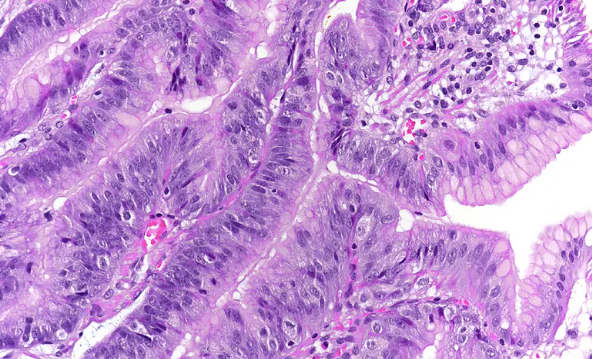

하지만 여기서 중요한 점은 단순한 혹(폴립)과 다르다는 것입니다. 위 선종은 세포 모양이 정상과 달라진 ‘이형성’ 단계입니다. 즉, 세포 구조가 변형된 상태로 암으로 발전할 가능성이 존재하는 병변입니다.

의학적으로는 다음처럼 구분됩니다.

- 저도 이형성 (Low-grade dysplasia)

- 고도 이형성 (High-grade dysplasia)

고도 이형성은 위암 직전 단계로 보는 경우도 있습니다.

4. 위 선종과 위암 차이 정확히 구분하기

구분 위 선종 위암 성격 양성 악성 전이 없음 가능 조직 침윤 없음 있음 치료 내시경 절제 가능 수술·항암 가능 👉 위 선종은 아직 암은 아닙니다.

👉 하지만 고도 이형성은 암과 경계가 매우 가깝습니다.